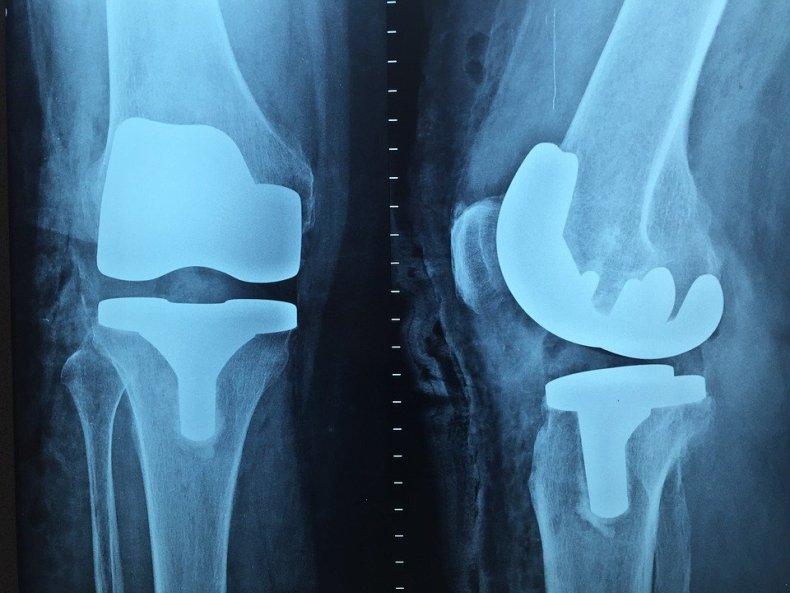

Рентген

Наиболее старый и привычный метод визуализации человеческого тела. Применяют рентген повсеместно, от хирургии до стоматологии. Метод прост и понятен: человека облучают особыми лучами, которые легко проходят сквозь мягкие ткани и задерживаются в твёрдых. Благодаря этому принципу, на фотоплёнку или датчик, расположенные на противоположной от источника лучей стороне, передаётся изображение, а в распоряжение врача попадает рентгенография или рентгеноскопия.

Главные плюсы такого обследования: быстрота и стоимость. Рентгеновскими аппаратами оснащены практически все больницы, процедура проходит быстро и стоит недорого.

Главные минусы: облучение и качество изображения. При проведении рентгенографии пациент облучается, а картинка получается двумерной. Врач с трудом может разглядеть внутренние органы по отдельности, поскольку их тени перекрывают друг друга. Также невозможно детально разглядеть хрящевую ткань и мозг. Хрящи практически не задерживает лучи, мозг надёжно закрыт черепной коробкой. Для их исследования рентгенография не подойдёт.

Наиболее эффективно будет проводить рентгенографию при повреждениях костей, суставов и зубов.